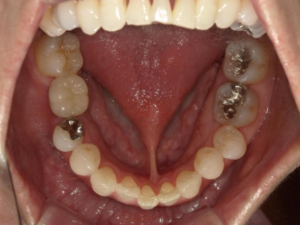

(治療後)

インプラントは単独での補綴物になるため、隣接歯への影響はなく、噛み合わせの再現もできる唯一の補綴物です。

▼第二治療終了後

経過も良好で、問題なく過ごしています。